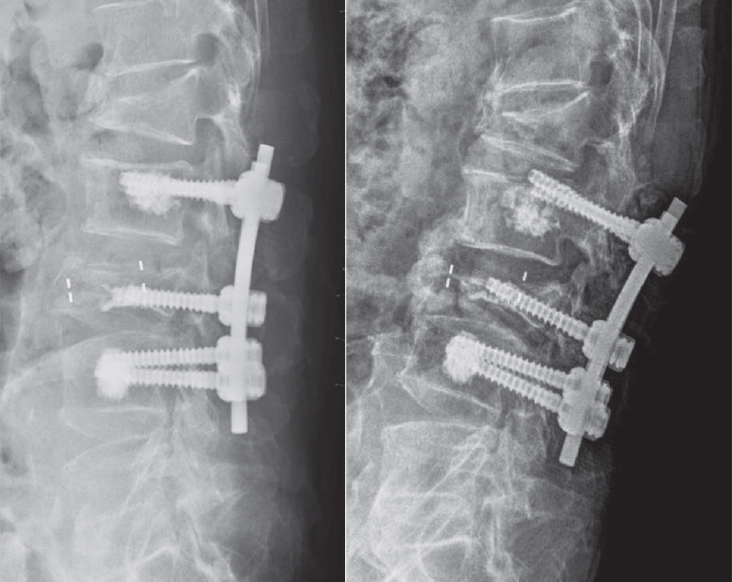

Reduction of Mechanical Failures After Thoracolumbar Fusion in Patients with Osteoporosis: The Role of Cement-Augmented Pedicle Screw

Woo-Sel Kim, Dal-Sung Ryu, Seung-Hwan Yoon J Adv Spine Surg 2025;15(2):63-70. -